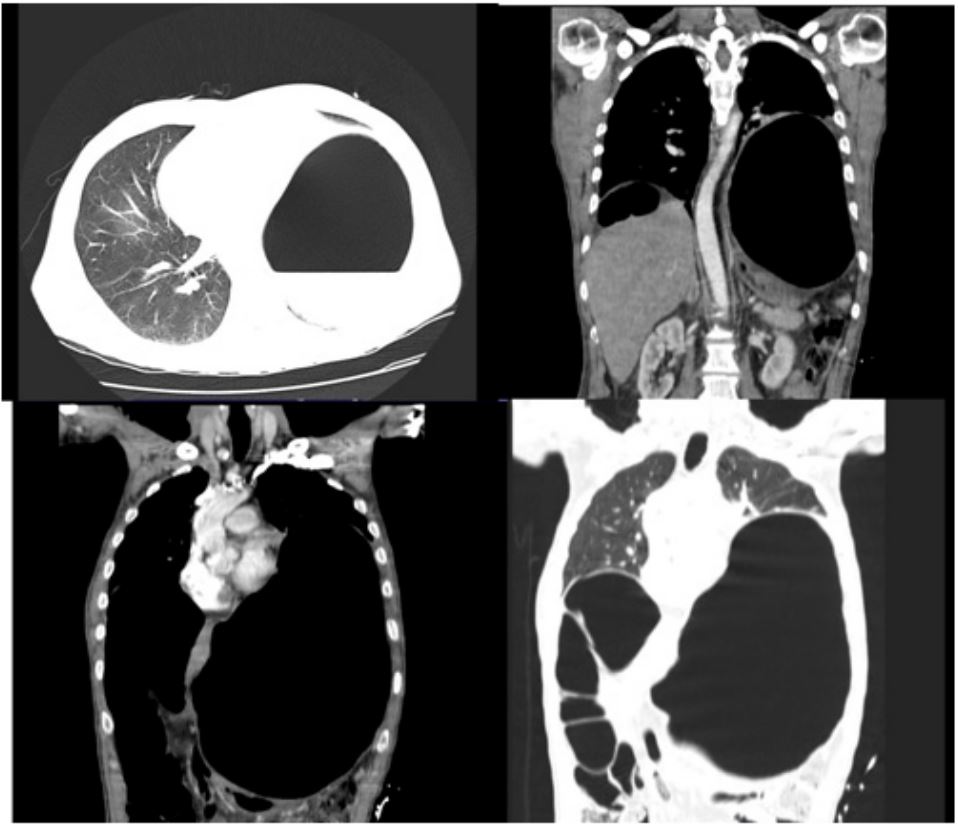

10 days later the patient returned to outpatient cardiology clinic for an echocardiogram and was noted to have a large pericardial effusion along with evidence of impaired relaxation of the left ventricle during diastole (Figure 1). Following transfer to the ED, he was noted to have a heart rate of 113 bpm and blood pressure of 129/70 mmHg; his respiratory rate, oxygen saturation and temperature were within normal limits. A chest x-ray ordered for his mild shortness of breath revealed a massively dilated, air-filled structure in the left upper quadrant with severe compression of the left lung and heart(Figure 2). A CT scan demonstrated massive dilation of a loop of bowel measuring 29 cm x 18 cm x 13 cm centered in the left upper quadrant with possible partial sigmoid volvulus (Figure 3).

Figure 1: Clinical image.